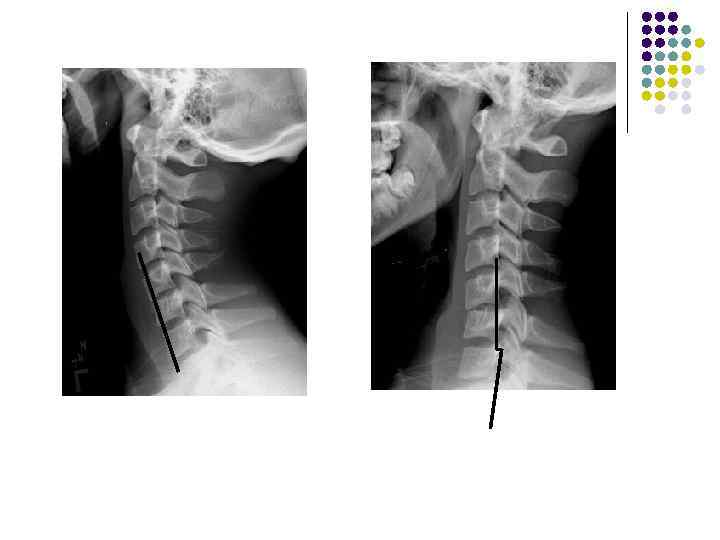

l l l На рентгенограмме шейного отдела позвоночного столба в боковой проекции определяется: выраженные дистрофические изменения за счет остеохондроза - значительное, неравномерное сужение межпозвонковых пространств с нарушением их правильной клиновидной формы, выраженный субхондральный остеосклероз, значительные костные разрастания по передним краям тел позвонков. Наиболее ярко эти изменения представлены в сегментах С-5, 6, 7. Помимо этого, в этих же сегментах фиксируются дистрофические изменения дугоотростчатых суставов – сужение рентгеновских суставных щелей, субхондральный остеосклероз и костные разрастания по краям суставных поверхностей. Выпрямление физиологического лордоза. Признаки системного нарушения статики тел позвонков в виде симптомов кифотической установки. Деструктивных изменений нет Заключение: Комплекс дистрофических изменений шейного отдела позвоночного столба в виде остеохондроза и артроза дугоотростчатых суставов с преимущественными проявлениями в нижних сегментах отдела. Нарушение статики тел позвонков

l На рентгенограмме шейного отдела позвоночного столба в боковой проекции определяется: выраженные дистрофические изменения за счет остеохондроза с преимущественными проявлениями в сегменте С 5 -6 – сужение и деформация межпозвонковых пространств, выраженный субхондральный остеосклероз, значительные костные разрастания по краям тел позвонков. Выпрямление физиологического лордоза. Признаки нарушения положения тела С 4 (симптом «распорки» )

l На рентгенограммах шейного отдела позвоночного столба в двух проекциях определяется комплекс выраженных дистрофических изменений с преимущественными проявлениями в сегментах С 5 -6 -7 в виде остеохондроза и выраженного спондилоза за счет неравномерного сужения межпозвонковых пространств, субхондрального отсеосклероза и костных разрастаний как по краям тел позвонков с продолжением плоскости замыкательной площадки, так и под передней продольной связкой с образованием мощного костного соединения. Положение тел позвонков правильное, деструктивных изменений нет.